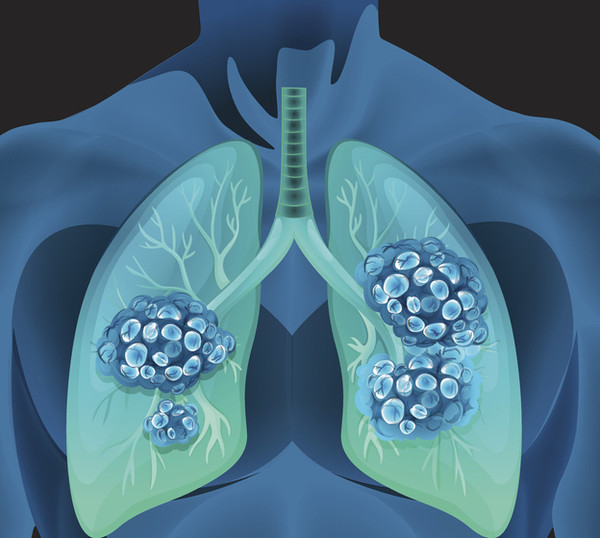

폐암 초기증상 12가지 총정리

이번 포스팅에는 폐암 초기증상에 대해서 알아보겠습니다.

폐암 초기증상 12가지